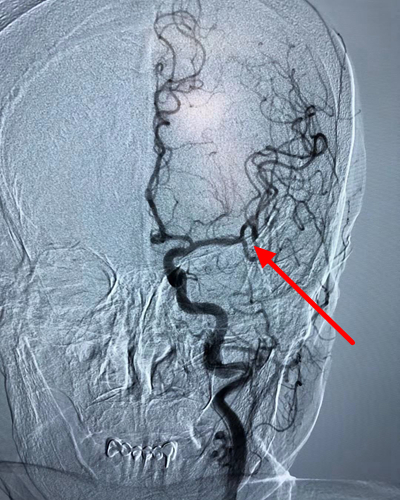

术后DSA箭头所示:左侧大脑中动脉已开通

经积极治疗后,左侧大脑中动脉闭塞的血管完全开通,患者言语及右侧肢体肌力恢复正常,家属非常感谢九院卒中中心及急诊科医护人员的全力救治,绿色通道机制,使患者得到及时有效的治疗,功能恢复非常满意。